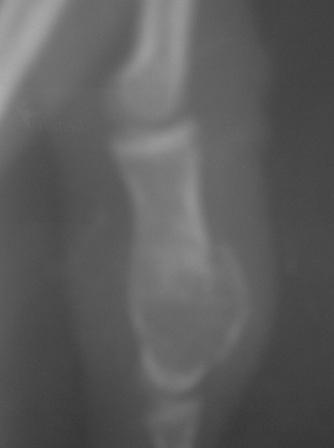

Уважаемые коллеги! Обратилась девочка 15 лет с жалобами на боли, отечности 4-го пальца кисти.

Заметила утолшение среднего фаланга 3 и 4-го пальцев 3,5-4 года назад, последний год начала чувствовать периодические боли, особенно в холодное дни, когда долго писала и всё. 4 дня назад получила легкий ожог пламенем кисти и пальцев, а 2 дня назад ударилась о волейбольный мяч и после этого в 4-м пальце нарастал отек , появилась резкая болезненность, усиливаюшийся при движении и пальпации, умеренная местная температура, а в 3-м пальце имеется утолшение среднего фаланга, следи ожога, безболезненный, отек м/тканей и местной температурй нет. Мы предполагаем ОБК, похоже и на фиброзную дисплазию, и краевой перелом сред. фаланга 4-го пальца и поэтому такая картина!

По рентгенограмме на ОБК не похоже.

Р-снимок прилагается.

С уважением Абдурашид.

Кликните для загрузки файла PICT0006.JPG

11KB (12015 bytes)

Послеоперационные x-ray некачественные, всё ж кое что можно разглядеть, постараюсь повторно снять!

Стояние довольно приличное. Хорошо, что сохранили суставы. В такой ситуации вообще-то ничего и не придумаешь, кроме спиц. Поэтому я бы не менял метода фиксации. По снимкам больше похоже было на энхондрому, но вот меня смущает белесоватый цвет содержимого и кашицеобразная консистенция. Подождем гистологии.

Гистологическое заключение- энхондрома!